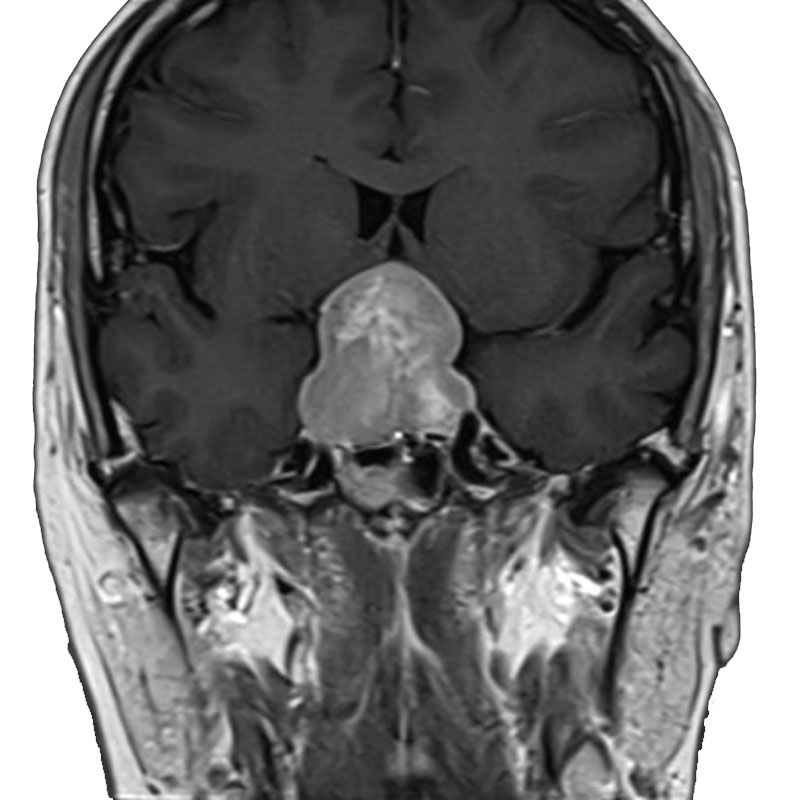

脳室内腫瘍

摘出術

北野/濵田